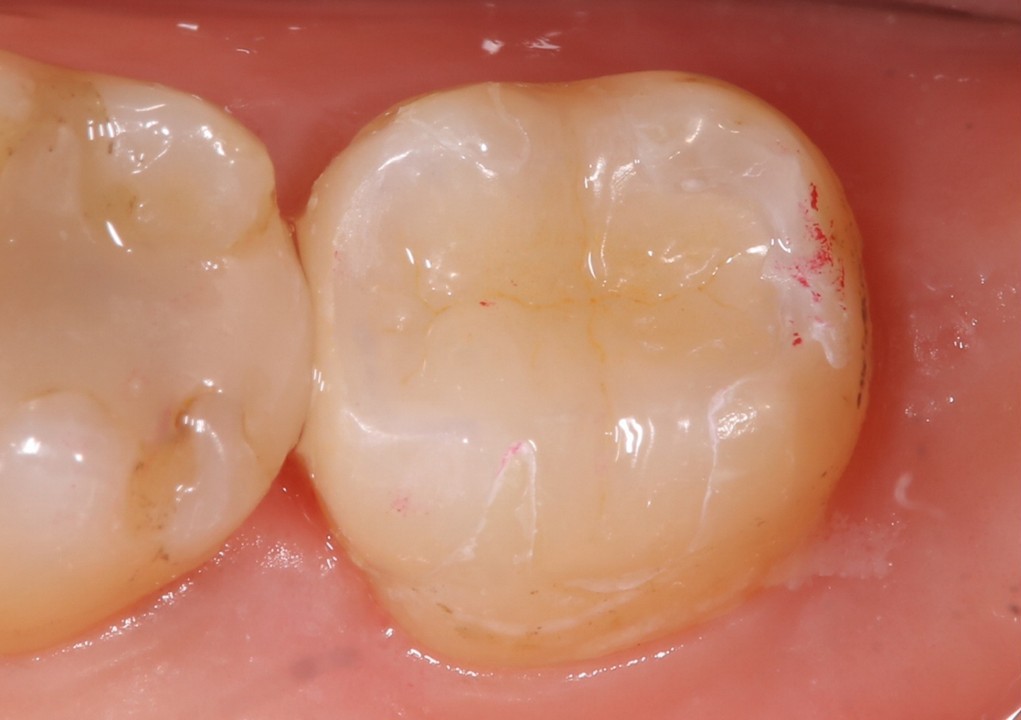

MTA貼付後、CRを用いて裏層し(図10)、修復処置を行う(図11・12)。

(図10)CRにて裏層

(図11)修復状態 エナメル質に近い硬さの材質を選択した